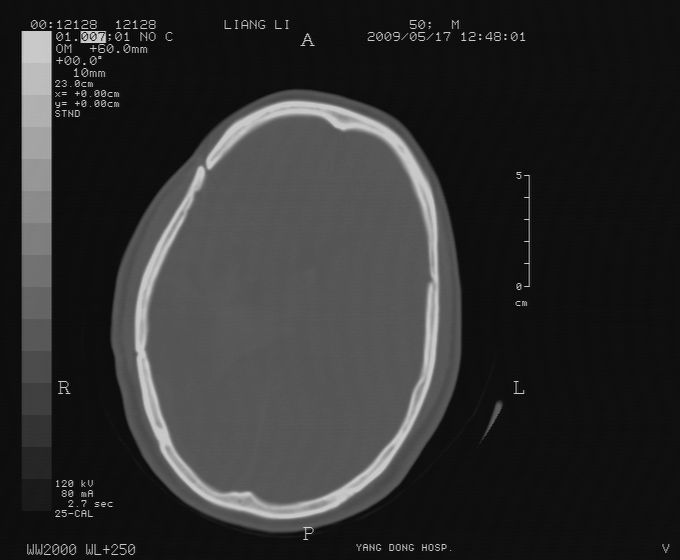

以下是引用zjzjr在2009-5-18 11:26:00的发言:[br]右颞枕叶及基底节区脑出血破入脑室系统,蛛网膜下腔出血,右枕顶部硬膜下血肿.颅骨及颅内低密度软化灶为血肿清除术后改变.

以下是引用随光逐影在2009-5-18 14:47:00的发言:[br]支持 右颞枕叶及基底节区脑出血破入脑室系统;蛛网膜下腔出血;右枕顶部及右侧天幕硬膜下血肿。右侧颅骨术后改变;颅内低密度软化灶为血肿清除术后改变。